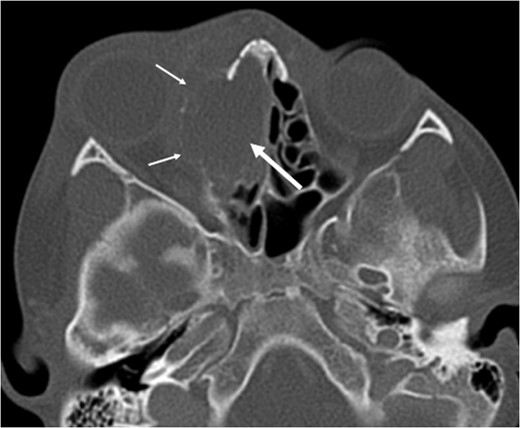

A 6-year-old boy with a background of asthma presented to a tertiary paediatric unit in May 2016 with a 3-day history of right eye pain, proptosis and erythema under the care of the ENT team. A provisional diagnosis of a periorbital cellulitis was made secondary to ethmoid sinusitis and management with intravenous antibiotics (ceftriaxone), intranasal steroids, saline douches and topical oxyxlometazoline was initiated. Ophthalmological assessment demonstrated normal colour vision, acuity and light reflexes bilaterally but also proptosis-related ophthalmoplegia. Computed tomography (CT) imaging of the orbits and paranasal sinuses demonstrated complete opacification of the right-sided paranasal sinuses and compromise of the right frontal and ostiomeatal unit. In addition there was an expansile abnormality centred on the ethmoidal labyrinth with bony remodelling of the lamina papyracea and a subperiosteal collection adjacent to the medial orbital wall (Figs 1 and 2). The most likely diagnosis was felt to be an infective process with mucopyocele formation complicated by a subperisoteal post-septal collection. An MRI scan with gadolinium of the orbits and sinuses confirmed the unilateral pattern of sinus opacification within the right frontal, ethmoids and maxillary sinus. The lesion demonstrated multiple fluid–fluid levels and peripheral enhancement (Figs 3 and 4). The patient was treated by endoscopic drainage of the lesion, which revealed only blood. He initially had some improvement of his proptosis but recurred within a few days and so further, more extensive endoscopic debridement was performed.

Axial non-contrast CT demonstrating an expansile lesion centred on the right-sided ethmoidal labyrinth (long white arrow) with remodelling of the lamina papyracea (short white arrows).